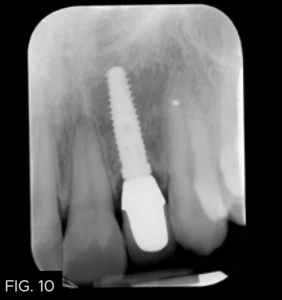

It was decided to place the abutment permanently and torque to 20 Ncm. Polytetrafluoroethylene tape was placed in the access cavity and composite (B1 Evanesce, Clinician’s Choice) was used to close the opening in the abutment. The crown was cemented (Temp-Bond, Kerr Dental). A radiograph was taken to ensure no subgingival cement was present. (FIG. 10)